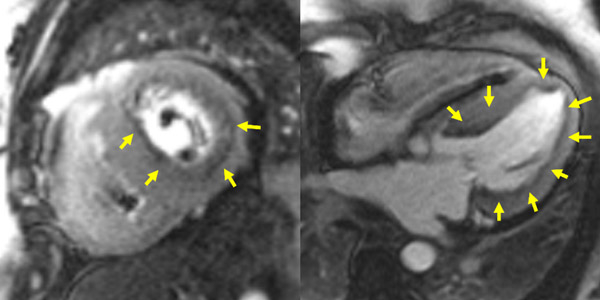

Figure 1A : Séquence Ciné-IRM - Coupes petit-axe basal

Figure 1B : Séquence Ciné-IRM - Coupes petit-axe médian

Figure 1C : Séquence Ciné-IRM - Coupes petit-axe apical

Figure 1D : Séquence Ciné-IRM - Coupes 2-cavités

Figure 1E : Séquence Ciné-IRM - Coupes 3-cavités

Figure 1F : Séquence Ciné-IRM - Coupes 4-cavités

Figure 5 : Séquence Ciné-IRM

- Présence d’une hypertrophie ventriculaire gauche (HVG) asymétrique à prédominance septale mesurée au maximum à 23 mm.

- Visualisation de la sonde de PM avec artéfacts métalliques modérés au niveau du ventricule droit (flèches roses).

- Présence d’un épanchement péricardique de moyenne abondance (flèches rouges).